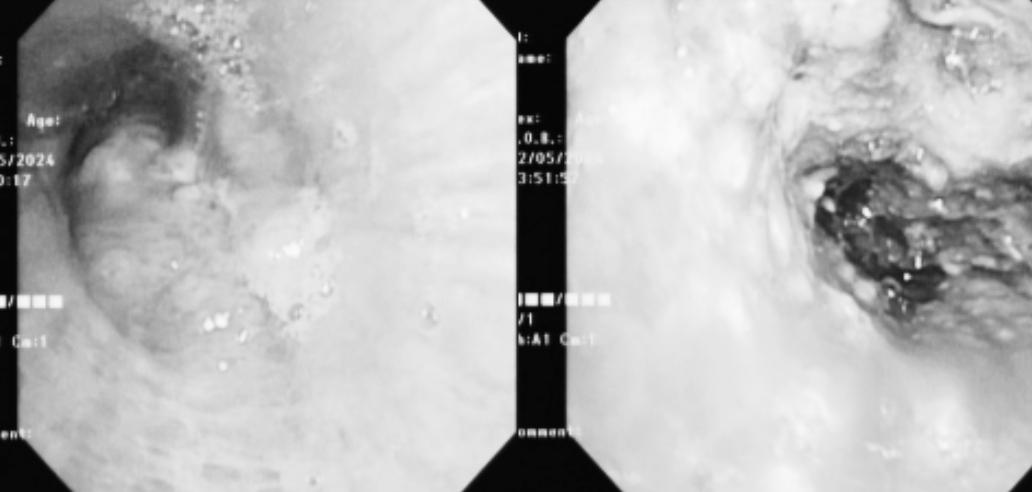

曾祥伯主任团队经过详细的评估准备,在呼吸内镜中心为患者进行了气管镜检查,立马就找到了周爷爷出现声嘶、吞咽困难和呼吸困难症状的元凶,支气管镜下显示,周爷爷的左主支气管重度狭窄,远端完全闭塞!

支气管镜根本不能通过,并且肿瘤供血丰富,稍触碰即有活动性出血,常规内镜操作大出血风险很高!

(治疗前:左主支气管大片新生物阻塞、治疗后:新生物阻塞面积缩小,左主支气管通畅)

3天后,第二次内镜治疗,左主支气管内肿瘤组织已经大部分坏死,镜下将坏死物取出后,左主支气管就恢复通畅了,并且没有出血。术后患者感觉呼吸困难得到缓解,术后第二天顺利出院。